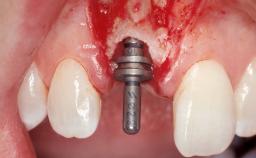

Immediate Flapless Placement of an Implant in a Maxillary Left Central Incisor Site

A 29-year-old female patient presented for treatment to replace the upper left central incisor tooth with an implant- supported restoration. The tooth had been intermittently symptomatic for the previous 12 months. The tooth had originally suffered trauma about 15 years previously. Several endodontic treatments had been performed, including an apicectomy procedure to retain the tooth. The patient was healthy and a non-smoker. She had reasonable expectations in regard to esthetic outcomes and the risk of marginal tissue recession following treatment. At medium smile, the gingival margins of the upper teeth were visible, with a display of 3 to 4 mm of the gingival margins. Gingival recession of tooth 21 and a discrepancy in the gingival levels between teeth 11 and 21 was observable during normal speech and smile.

Placement Protocol Immediate implant placement

Tooth Site Maxillary incisor or canine

Socket Integrity Damage to one or more bone walls

Loading Protocol Conventional or early